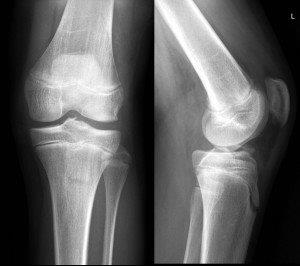

Patella sleeve fracture. The patient clinically had difficulty extending knee (above)